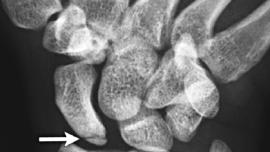

Artificial intelligence improves wrist fracture detection